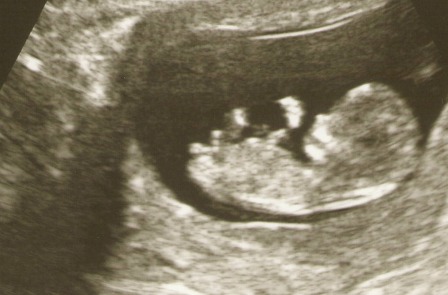

Megvannak a sztárfotók! kiderül, hogy 13 hetes vagyok, szóval nekem nagyon április eleje lesz :)

Kép Pocaklakó

Kép

Az alsón, mint egy párnára fekszik a méhlepényre! :)

Sokat mocorgott és még csuklott is! Édes, nem?